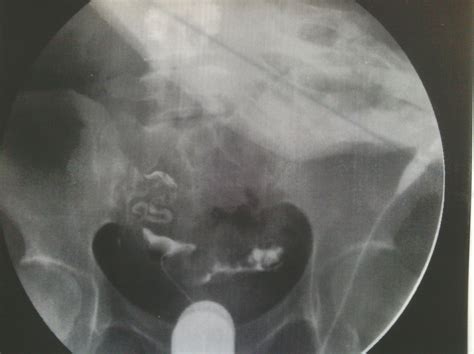

输卵管堵塞的早期一般都是没有任何反应的,只有少数人可能会觉得肚子隐隐作痛,一旦输卵管发炎,肚子就会痛得厉害了,很多人才去就医。如果你备孕长久不成功,可以通过输卵管造影检查自己的输卵管是否畅通。